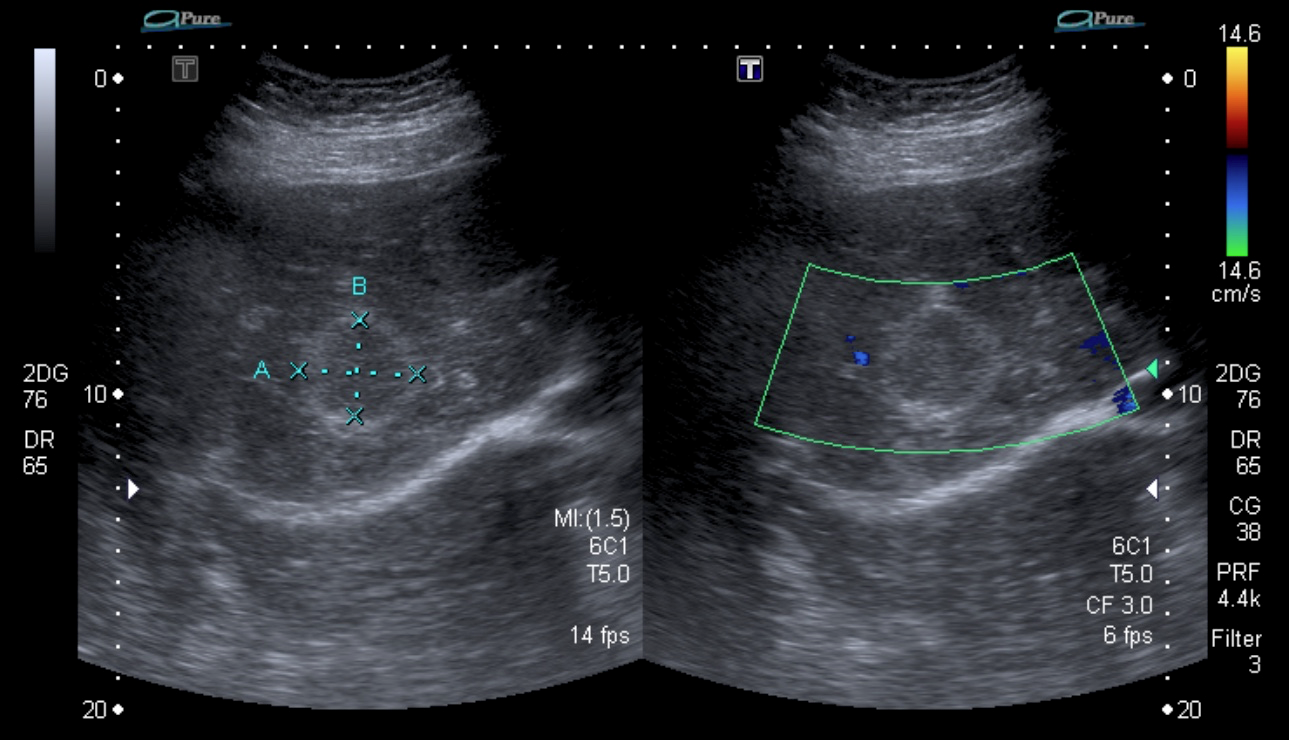

Paciente de 72 años con antecedente de tuberculosis genitourinaria hace 40 años.